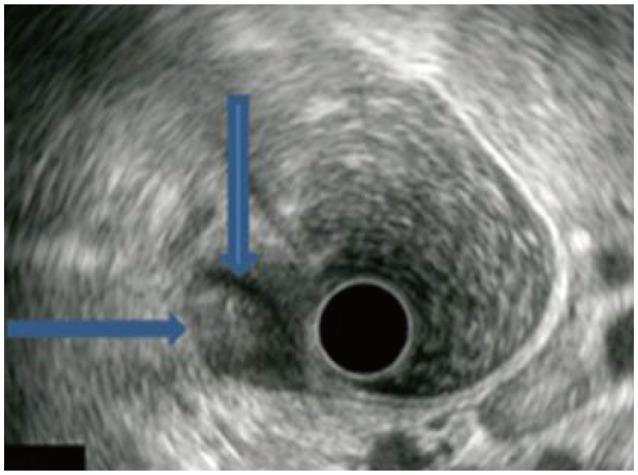

Granular cell tumor (GCT) is an uncommon, usually benign neoplasm; however, a malignant potential has been described. Malignant GCT is an extremely rare neoplasm showing rapid growth and invasion into adjacent muscles, lymph nodes, or vessels, or even distant metastasis. We recently experienced a case of a histologically benign or atypical but clinically malignant GCT, with invasion of the lymph nodes and vessels in the sigmoid colon, diagnosed by segmental colon resection with lymph node dissection. We also performed a review of relevant medical literature.

颗粒细胞瘤(GCT)是一种罕见的、通常为良性的肿瘤;然而,也有文献描述其具有恶变潜能。恶性颗粒细胞瘤是一种极其罕见的肿瘤,表现为生长迅速,并侵犯邻近肌肉、淋巴结或血管,甚至发生远处转移。我们最近遇到一例组织学上为良性或非典型但临床上为恶性的颗粒细胞瘤病例,该肿瘤侵犯了乙状结肠的淋巴结和血管,通过结肠节段切除加淋巴结清扫得以确诊。我们还对相关医学文献进行了回顾。